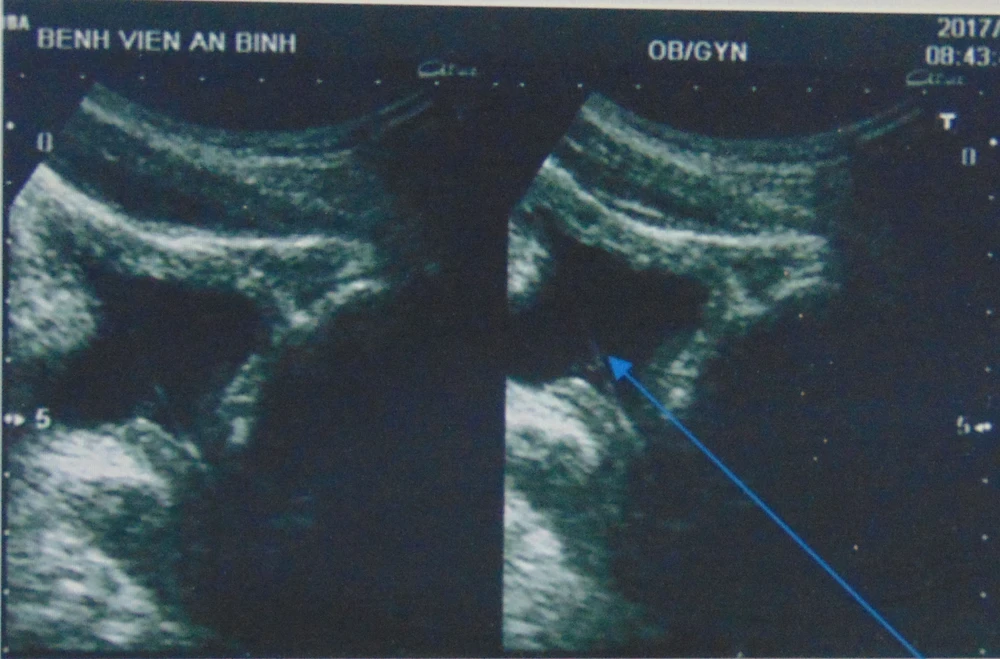

Kết quả siêu âm ghi nhận có một dị vật nằm trong bàng quang (hình mũi tên). Ảnh: NHẬT ĐÔNG

Sau khi siêu âm, các BS không phát hiện thấy sỏi thận ở lỗ tiểu. Bệnh nhân cũng hết đau và không còn tiểu ra máu. Tuy nhiên, các BS lại phát hiện có một dị vật mỏng, dài 2 cm trên đường từ niệu đạo tới bàng quang. "Dị vật là một mẩu của cọng cỏ. Bình thường, với dị vật kẹt trong bàng quang, các BS sẽ phải can thiệp để lấy ra. Nhưng may mắn là ở bệnh nhân này, mẩu cọng cỏ ngay sau đó đã được tống ra ngoài theo đường tiểu" - BS Đông cho biết thêm.